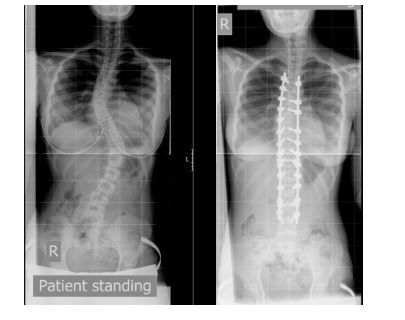

אבחון חומרת העקמת מבוצע בצילום עמוד השדרה לכל אורכו. צילום זה צריך להתבצע על קסטה ארוכה ואינו זמין בחלק ממכוני הרנטגן. ניתן לקבל גם מושג באשר לגיל העצמות, נתון החשוב לצורך החלטה על הטיפול.

הגישה האחורית היא הגישה המשמשת למרבית המצבים. בגישה זו המטופל/ת שוכבים על הבטן בזמן הניתוח. מבוצע חתך ישר במרכז הגב, שאורכו תלוי במספר החוליות הנכללות בקיבוע. המנתח מתקין נקודות עגינה לחוליות אשר מבוססות על ברגים, ו 2 מוטות אשר חיבורם לנקודות העגינה מאפשר הפעלת מניפולציה על עמוד השדרה הגורמת לתיקון העקמת. לאחר בצוע התיקון המנתח משתיל עצם על גבי החוליות והרקמות נתפרות למקומן. תמונות 2 ו- 3 מציגות עקמת לפני ואחרי תיקון בגישה אחורית.